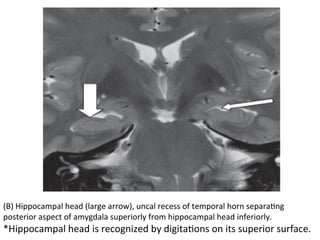

Coronal	T2	MR	images(a,b,c)	from	anterior	to	posterior,

demonstraHng	the	main	limbic	structures	of	the	mesial

(B)	Hippocampal	head	(large	arrow),	uncal	recess	of	temporal	horn	separaHng

posterior	aspect	of	amygdala	superiorly	from	hippocampal	head	inferiorly.

*Hippocampal	head	is	recognized	by	digitaHons	on	its	superior	surface.